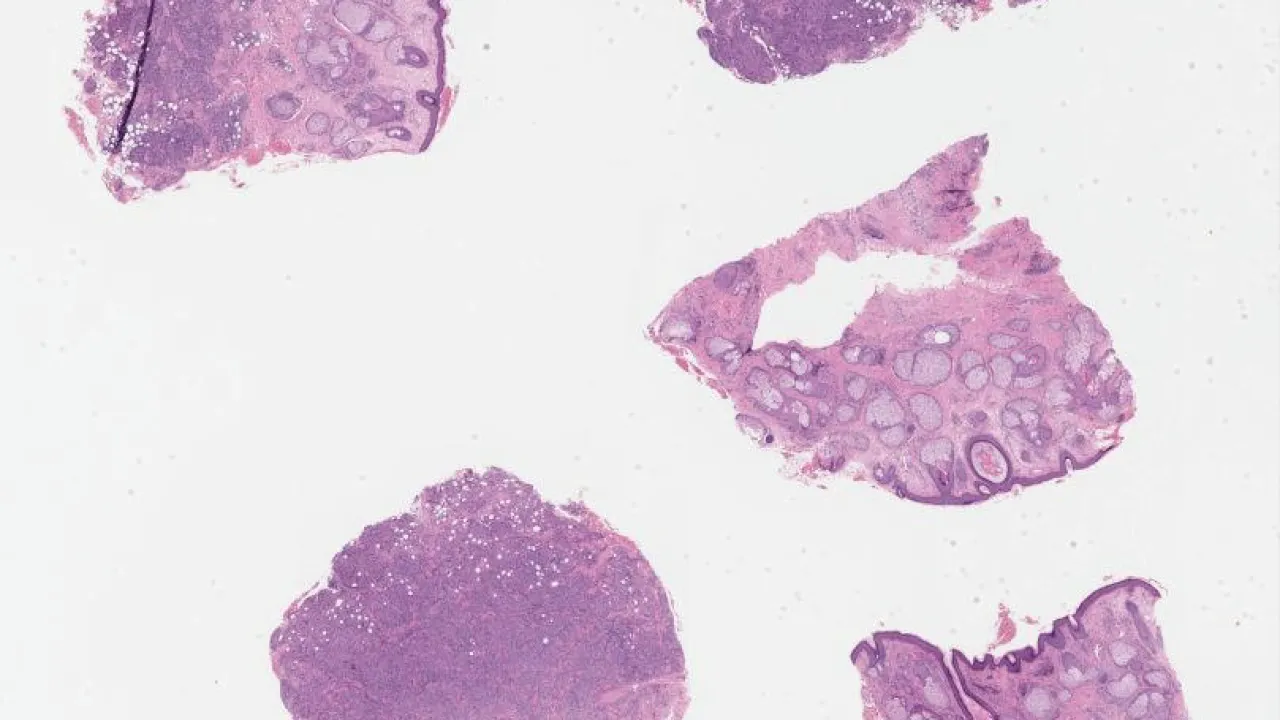

Parotid gland, Warthin tumour